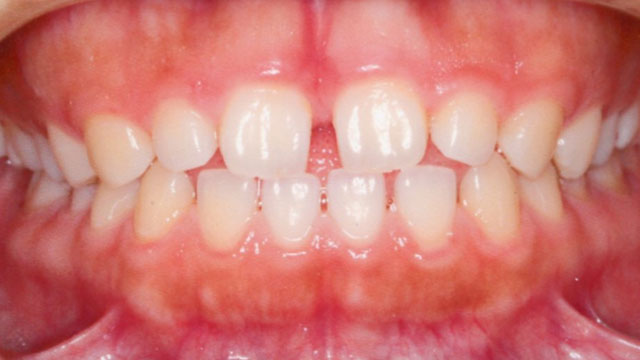

症例02【空隙歯列】

16歳9か月(男子)

上下の顎の成長・発育のバランスには問題はなく、骨格的な不調和は認められませんでした。

ただし、歯の大きさが平均よりもやや小さいことに加え、舌で前歯を押し出す癖(舌突出癖)がみられ、これが前歯の位置に影響している状態でした。

- 主訴

- 前歯の隙間、発音しにくさ

- 診断名

- 空隙歯列